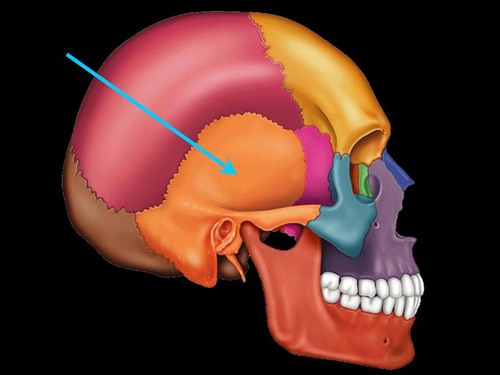

saggital suture